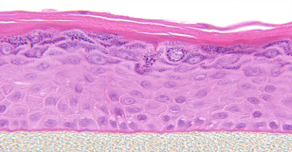

EpiDerm™由正常的人体表皮形成细胞培养形成的具备多层高度分化的重建人类表皮模型。该模型使用志愿者们提供的人源表皮角质形成细胞(NHEK)在特殊的无血清培养体系中培养形成,在组织结构上与人类皮肤表皮具有高度相似形。EpiDerm TM 经过多项ECVAM验证,并已被纳入OECD测试指南,适用于各类化学品、农药、药品和护肤品的体外测试。

表皮层呈现出人类表皮组织结构和细胞形态。

基底层细胞排列有序,有增殖能力;同时还有棘层、颗粒层、角质层。